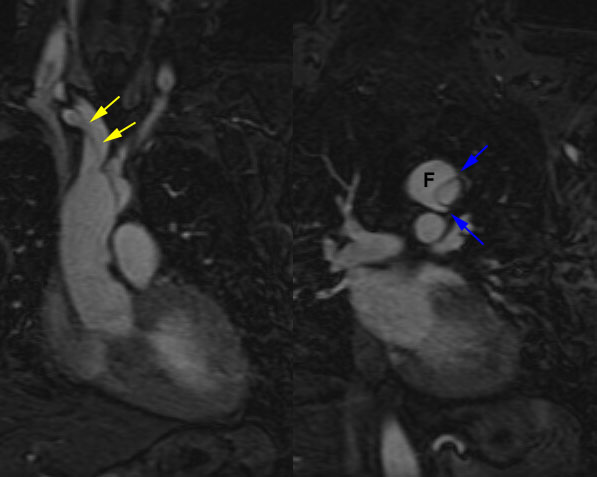

Scott WilliamsLymphoproliferativeLymph > Lymphoma > GeneralApril 2, 2002Inhalation-LungsInhale > Asbestos > Images > Round atelectasis typical appearance case 1April 2, 2002Mediastinal MassesMediastinum > GneuroblastomaApril 2, 2002Inhalation-LungsInhale > AsbestosApril 2, 2002Infections-InflammatoryInfect > Parasites > PCP > Images > ClassicApril 2, 2002EndocrineEndocrine > Thyroid > Imaging TestsApril 2, 2002Radiation BiologyRadiation biologyApril 2, 2002AutoimmuneAutoimmune > PIEApril 2, 2002GastrointentinalGastrointestinal > MotilityApril 2, 2002Vascular AbnormalitiesVascular > Dissection > Images > TypeA > Case1April 2, 2002Previous PagePage 103 of 265Next PageTop StoriesDigital X-RayChest x-rays reveal atherosclerosis in patients undergoing amputationsLower limb amputation is an increasingly common major complication of advanced peripheral arterial disease and diabetes mellitus.MRI3D MRI technique helps plan treatment for pediatric heart conditionsWomens ImagingCould AI scoring help with managing DCIS?CTClinicians, beware: CT diagnostic accuracy varies by adnexal lesion typePractice ManagementRadiology coding update for 2026